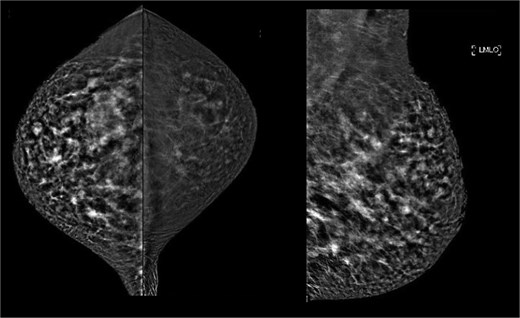

This was a 49-year-old lady of Philippine descent with previous free silicone injections in bilateral breasts in 1996. She was seen in the breast surgery clinic in October 2015 for a right breast lump in the upper outer quadrant. Mammogram showed extremely dense bilateral breasts with multiple dense oval opacities compatible with free silicone (Fig. 1). Ultrasound revealed a snowstorm appearance, with round cystic lesions scattered throughout both breasts representing silicone granuloma (Fig. 2). She was reassured at the time.

October 2015: Mammography images; craniocaudal views (left), mediolateral oblique views (right).